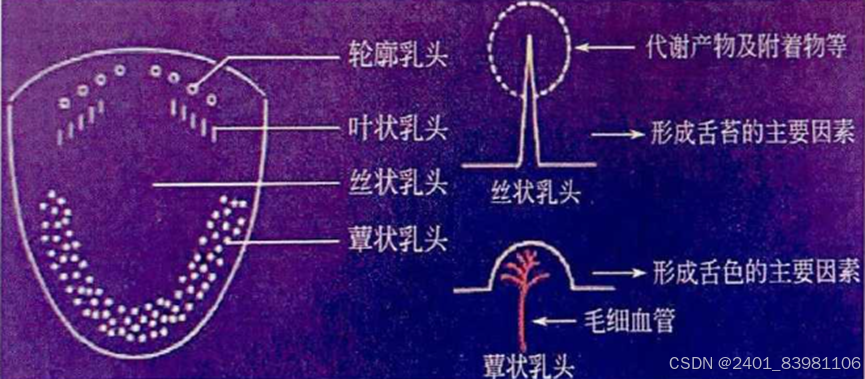

三:乳头分类识别

让患者口含具有苦味强调的标准样品,通过标注注释识别分类(基于深度学习的机器图像识别)如下时一种基于卷积神经网络的机器学习图像处理方法示例:(深度学习方法在乳头客观化方面缺乏突破)

操作:训练有素的操作员对舌头的特定部位进行视觉识别和手动计数(自动图像分析方法);

有待研究